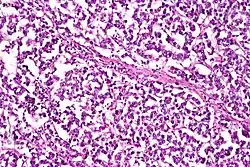

A micrograph showing yolk sac tumour, with smooth external surface and capsule tears

The ovarian yolk sac tumors, also known as endodermal sinus tumors, are accountable for approximately 15.5% of all OGCTs.[8] They have been observed in women particularly in their early ages, and rarely after 40 years of age.[9] The critical pathologic features are a smooth external surface and capsular tears due to their rapid rate of growth. A study consisting of 71 individual cases of ovarian yolk sac tumor provides evidence to the proliferation of the tumor. In one of the cases, the pelvic examination revealed normal activity until a 9 cm and 12 cm sized tumor was discovered 4 weeks later.[9] In another case, a 23 cm tumor was discovered in a pregnant woman who was monitored regularly and had normal findings until oophorectomy became essential.[9] Histologically, these tumors are characterized by mixed solid and cystic components.[1] The mixed solid components are characterized by a soft gray to yellow solid components accompanied with significant hemorrhage and necrosis. The cysts are approximately 2 cm in diameter and populated throughout the tissue which results in giving the neoplasm a ‘honeycombed appearance’.[1]